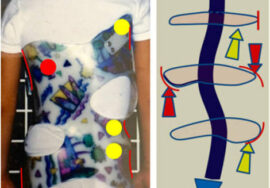

الحزام (أو الدعامة الطبية) يُعد من أهم الوسائل غير الجراحية لتصحيح أو تثبيت الانحناء، لكن فعاليته تعتمد على الالتزام بالمدة المحددة يوميًا.

بعض المرضى يخطئون بعدم ارتداء الحزام إلا لبضع ساعات، أو يخلعونه أثناء النوم أو المدرسة، مما يقلل فعاليته.

التزمي بتعليمات الطبيب حول عدد ساعات ارتداء الحزام (غالبًا بين 18 إلى 23 ساعة يوميًا).

احرصي على متابعة بشرة الطفل لتجنب الاحمرار أو التهيج، مع تنظيف الحزام بانتظام.

أحدث التقنيات العالمية: نعتمد على تقنيات حديثة مثل أجهزة التقييم الدقيقة وأحزمة التقويم المتقدمة مثل PioBrace.